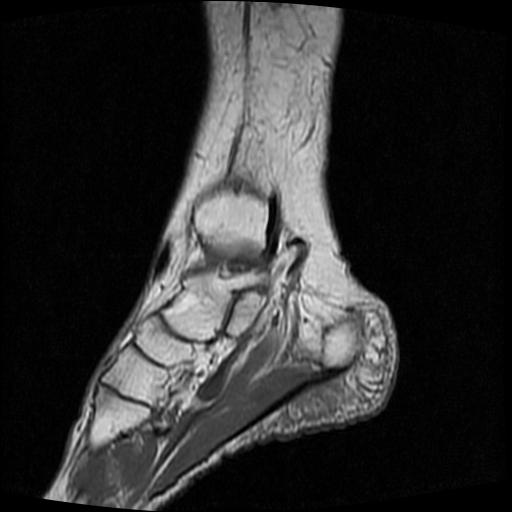

女性,70岁,右侧跟骨疼痛2个月,负重时加剧,不负重时不疼。

胫骨下段,跟骨、距骨可见斑片状异常信号区;考虑:转移瘤

跟骨长t1长t2信号异常,边缘模糊(肿瘤一般边界清楚,故肿瘤不考虑),压脂像呈高信号--骨髓水肿(炎症?)。